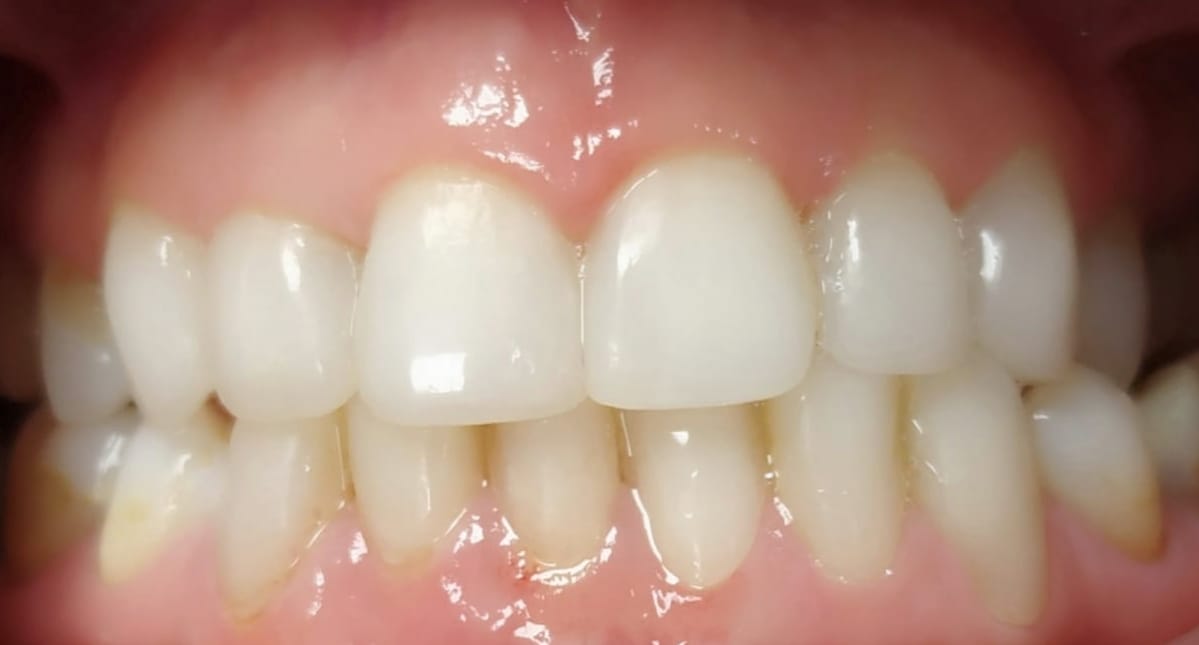

12 urtetik aurrera, egiturak ondo eratuta daudenean, hortzak lerrokatzen eta berdintzen saiatzen gara, irribarre eder eta osasungarria lortzeko.

Gure tratamendu ortodontzikoak problema funtzionalak ebaztean edo irtenbide estetikoak ematean oinarritzen dira, beti nahi izan duzun irribarrea erakusteko.

Kasuak

Ortodontzia